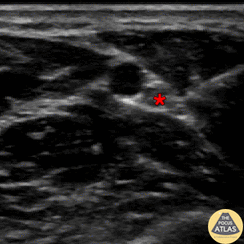

In-plane ulnar nerve block with needle seen entering from the ulnar aspect, depositing anesthetic first in soft tissues, followed by injection adjacent to the ulnar nerve (*). The ulnar artery can be seen pulsating screen left (radial to) the nerve. Denver Health Ultrasound Fellowship Archive